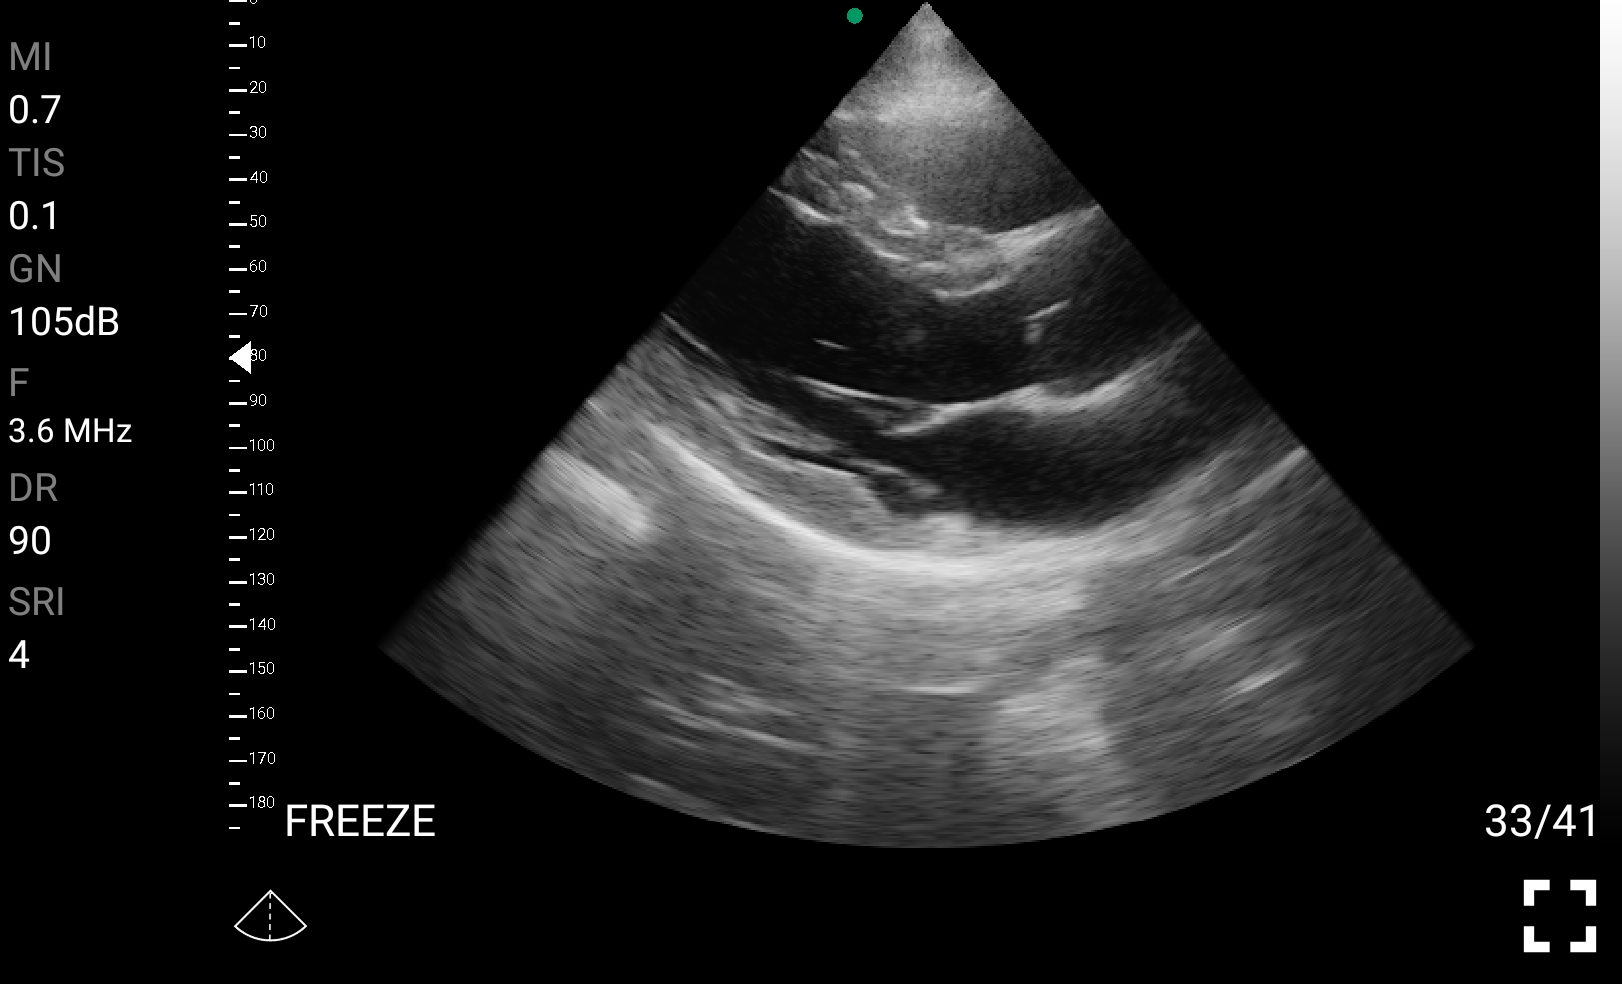

• Καρδιολογική Απεικόνιση για Κλινική Αξιολόγηση

• Εκτίμηση κλάσματος εξώθησης (EF): Προσέγγιση της συστολικής λειτουργίας της αριστερής κοιλίας.

• Διάγνωση περικαρδιακής συλλογής: Εκτίμηση πιθανής καρδιακής επιπωματισμού.

Παραδείγματα

Ολες οι παραπάνω απεικονιστικές εξετάσεις έχουν ληφθεί από φορητή συσκευή όπως: Apple Iphone, Tablet, Samsung Mobile Phones και διάφορες άλλες φορητές συσκευές.

Παραδείγματα Video